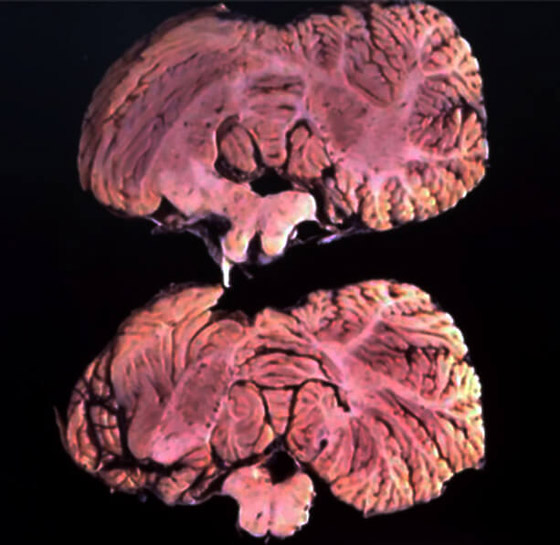

داء "كورو" أو داء "الضحك المميت" أو كما يسميه الأطباء "اعتلال الدّماغ الاسفنجي المتنقل"، بدأ في الانتشار في عام 1957 لكن لم يتم تشخيصه حتى عام 1976 على يد الطبيب الأمريكي كارلتون جايدوشك، والذي حاز على جائزة نوبل لاكتشافه هذا المرض. وقد سمي بهذا الاسم نظراً للرعشة الشديدة التي تصيب المرضى بهذا الداء، إذ إن كلمة "كورو" تعني "الاهتزاز".

ينتقل "كورو" عبر أكل لحوم البشر، تحديداً الأدمغة، وهو عبارة عن فيروس يصيب الجهاز العصبي المركزي، ويدخل المريض في نوبة مفاجئة من الضحك الهستيري، ويتطور إلى رعشة مستمرة في جسد المريض مع ألم في الرأس والعظام والمفاصل، وبمرور الوقت يصبح المريض عاجزاً عن الحركة حتى عند البلع والتنفس. وسينتهي أمر المريض بالنهاية إلى الموت خلال سنة واحدة من ظهور الأعراض كأبعد تقدير.